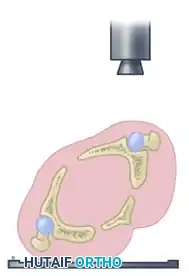

Technique for Measuring Roof Arcs

The roof arc is measured across the three standard radiographic views. A vertical reference line is drawn through the geometric center of the acetabulum. A second line is drawn from the geometric center to the point where the fracture line intersects the intact acetabular roof. The angle formed between these two lines is the roof arc.

- Medial Roof Arc: Measured on the AP pelvis view. Evaluates the superior-medial aspect of the dome.

- Anterior Roof Arc: Measured on the Obturator Oblique view. Evaluates the superior-anterior aspect of the dome.

- Posterior Roof Arc: Measured on the Iliac Oblique view. Evaluates the superior-posterior aspect of the dome.

Surgical Indication Warning: According to the biomechanical principles established by Matta et al., if any of the three roof arc measurements in a displaced fracture are less than 45 degrees, the critical weight-bearing dome is compromised, and operative treatment (ORIF) should be strongly considered to prevent rapid post-traumatic arthrosis.